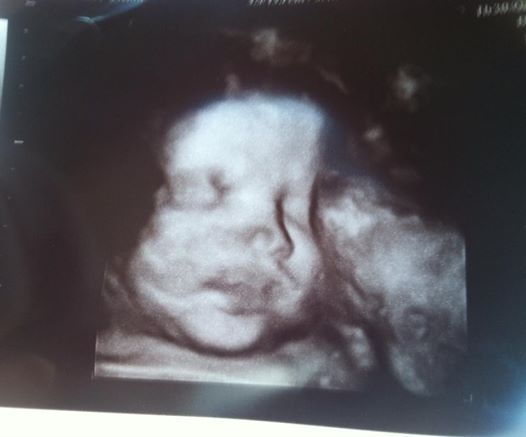

35 weeks w/sono pic

Just came back from my 35 week apt. DS was in a great spot so the tech turned on the 3d so we could get a lil sneak peak!! My boy is a chunky monkey weighing in at 6 1/2 pounds lol... Lord my luck hes going to be a 10 pound baby!! haha

what a cutie!!! Look at those lips!